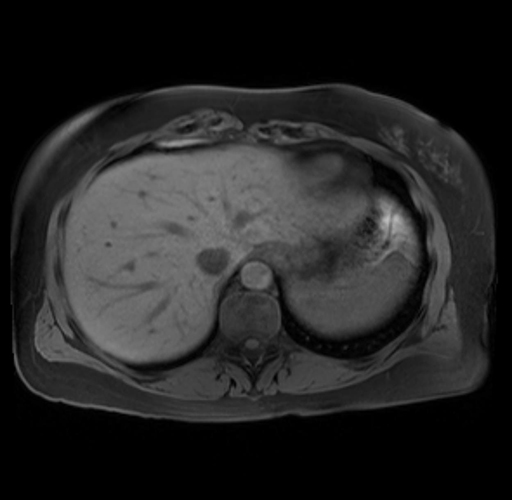

Imaging Analysis

Look through the patient's CT scan to identify any areas of concern for the necessary procedure.

Based on your CT findings, which issue(s) are present and would give reason for "planned slowing down moment(s)" in this case?